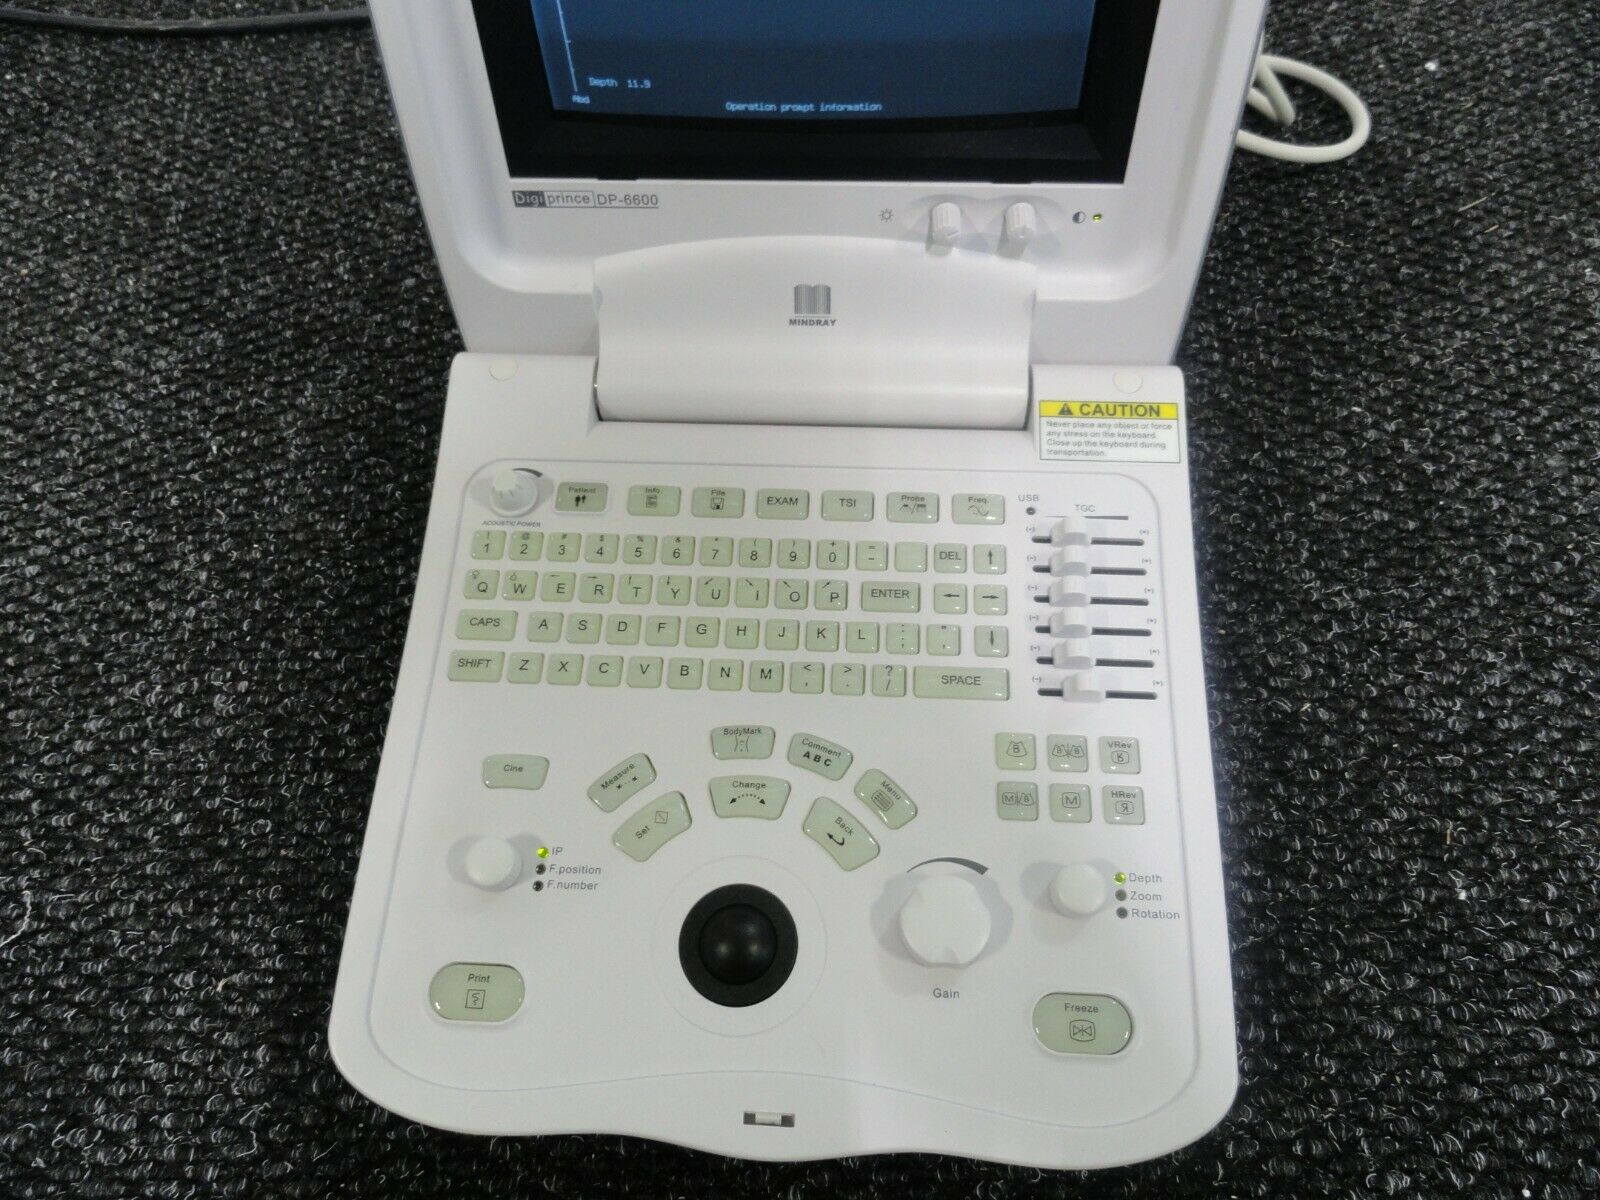

Mindray DigiPrince DP-6600 Ultrasound Machine with Transducer

Sale price$ 10,492.00

Regular price$ 11,192.00

Save $ 350.00

Mindray DP-6600 Digital Portable Ultrasound with Linear Probe Transducer

Sale price$ 2,550.00

Regular price$ 2,720.00

MINDRAY DP-6600 ULTRASOUND SYSTEM + 2 TRANSDUCER

Sale price$ 8,628.99

Save $ 550.00